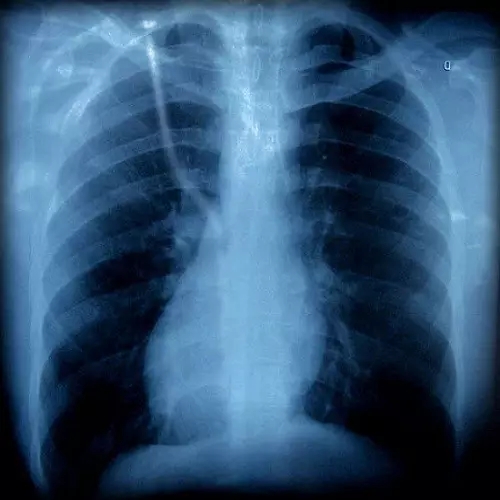

胸片有異

胸外科

咳嗽可以是由肺部腫瘤等疾病引起的,如果胸片或胸部CT上發(fā)現(xiàn)有可疑病變時,應(yīng)該看看胸外科。一般,呼吸內(nèi)科大夫也會幫忙轉(zhuǎn)診的。